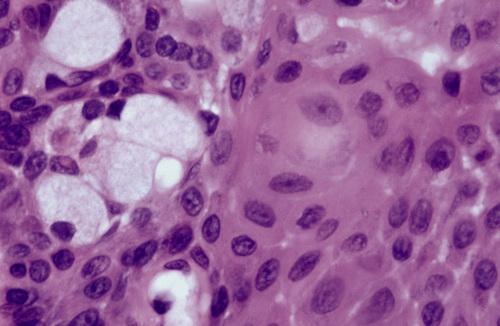

Histopathological Features

- lymphocytic infiltration of salivary glands

- destruction of acinar units

- hyperplastic ductal and myoepithelial cells

- groups of cells ("epimyoepithelial islands")

Lymphocytic infiltrate of the parotid gland with an associated epimyoepithelial island. Lymphocytic infiltration of the minor glands also occurs, although epimyoepithelial islands are rarely seen in this location.

Sjögren syndrome

Labial gland biopsy showing multiple lymphocytic foci. A focus score ≥ 1 (i.e. one or more foci of 50 or more cells per 4-mm2 area of glandular tissue) is considered supportive of the diagnosis of this disease.

Sjögren syndrome